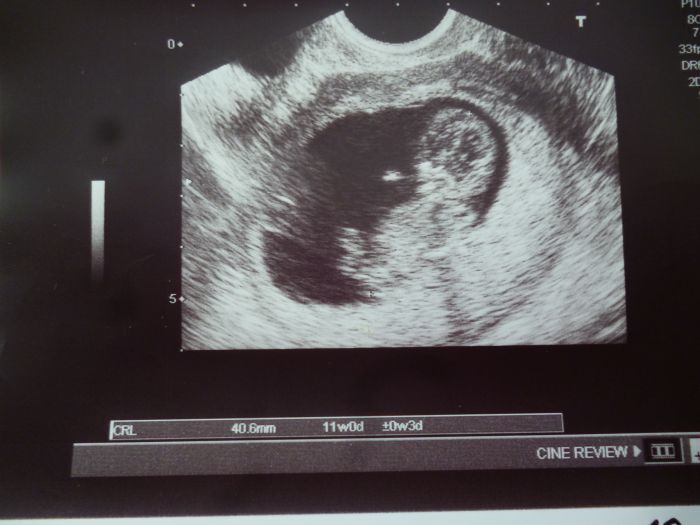

Holky tak výsledky super,jsem 10+6 takže 11 tt,mimi má 4 cm a zhruba 7 gramů a vše vpořádku,žádné genetické vady nebyli nalezeny,i u srdíčka vše vpořádku,tak jsem si oddychla,jen se mu zdálo,že mám méně plodové vody,ale to se prý upraví,za 10 dní jdu ještě jednou na UTZ,to budu konec 12 tt.

[1013615] Mirko, moc gratuluju a fotka je nádherná!!! Ty jo, úplně mě to dojalo...takže ty jsi už byla na screeningu nebo jakto všechno už víš? "A na kdy ti tedy vychází termín porodu, nebude to spíš únor? Tak to jsi asi že všech nejdál:-)ještě jednou moc gratuluju, je to krása.